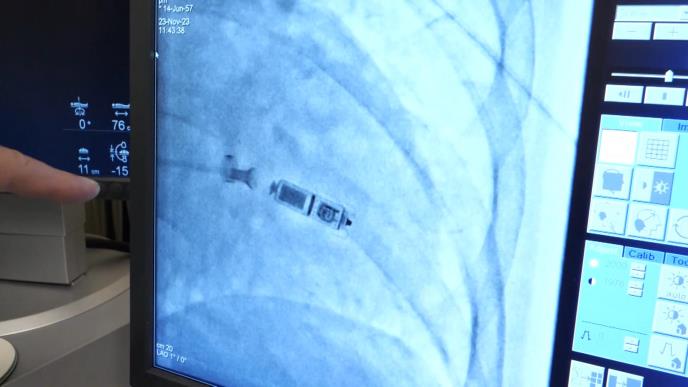

Televizija Kurir prisustvovala je ugradnji minijaturnog pejsmejkera, u operacionoj sali Univerzitetskog kliničkog centra Niš! Ovaj mikro pejsmejker se ugrađuje direktno unutar srčanog mišića kroz femoralnu venu i naročito je važan za pacijente kod kojih klasična operacija nosi veliki rizik

Taj mikro pejsemejker ugrađuje se, kažu, direktno unutar srčanog mišića, kroz femoralnu venu, i posebno je važan za pacijente kod kojih klasična operacija nosi veliki rizik.

Bez klasičnog operativnog reza, ovaj metod donosi velike benefite pacijentima koji su podložni riziku prilikom ugradnje klasičnog pacemakera. Smanjuje se trauma, a rizik od infekcije džepa u koji se aparat ugrađuje je takođe manji. Ovo je kratko definisana intervencija ugradnje minijaturnog pacemakera, koja se uspešno izvodi u Nišu u poslednje vreme.

- Iako nema mnogo ovakvih pacijenata, važno je napomenuti da je ovo strogo indikovana procedura, visoko specifična. Do danas smo izveli 12 ovakvih procedura ove godine, a pacijenti koji su indikovani dobijaju termin u roku od mesec dana - rekao je profesor dr. Tomislav Kostić direktor klinike za kardiologiju.